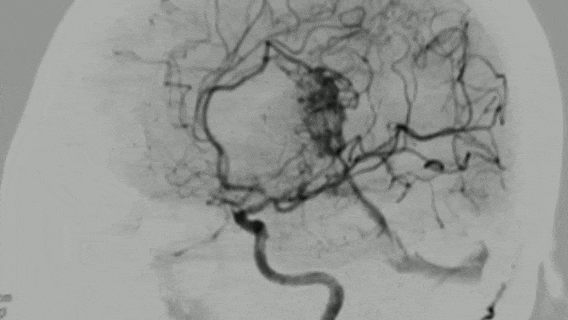

与一些紧密的AVM不同,小蕊的AVM非常弥散,有多条血管从不同区域供血,包括前动脉循环和后动脉循环,增加了手术的复杂性。

致密型动静脉畸形好比一团缠得紧紧的毛线球,核心明确,边缘清晰。与周围正常的脑组织之间界限相对分明。在脑血管造影(DSA)上看起来是一个相对局限、浓密的染色区。

异常的血管分散、浸润性地生长在正常的脑组织中,没有明确的边界。与正常脑组织交织在一起,好比把墨水洒在吸水的海绵上,界限模煳。在DSA上表现为范围较广、染色较淡且边界不清的区域。